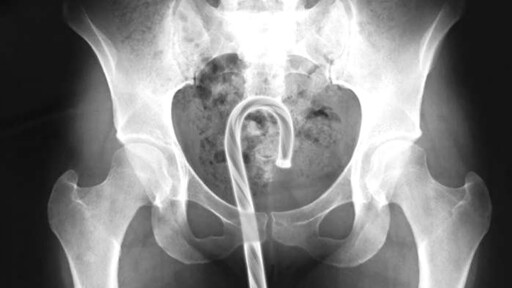

What Did We Get Stuck In Our Rectums Last Year? | Defector

This is the time of year to be grateful for not having things stuck in our asses, and to think of those less fortunate than us. So spare a thought for those Americans who misjudged the capacity of their own orifices. All reports are taken from the U.S. Consumer Product Safety Commission’s database of emergency room visits,…